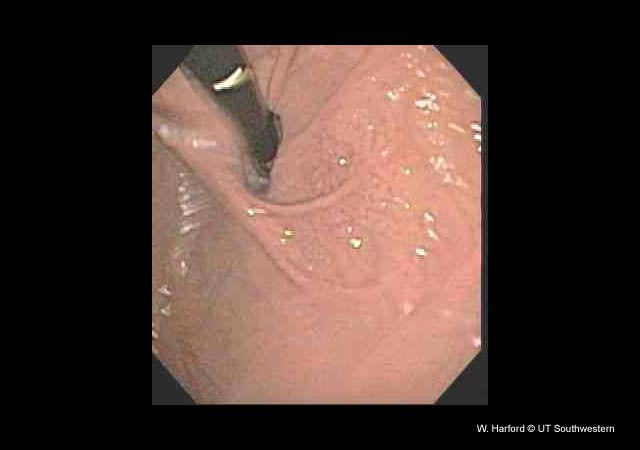

ESOPHAGUS, STOMACH, AND DUODENUM Case #5 - A 65 year old with hematemesis    Go to previous image Go to next image

Esophagoscopy showing normal gastric cardia